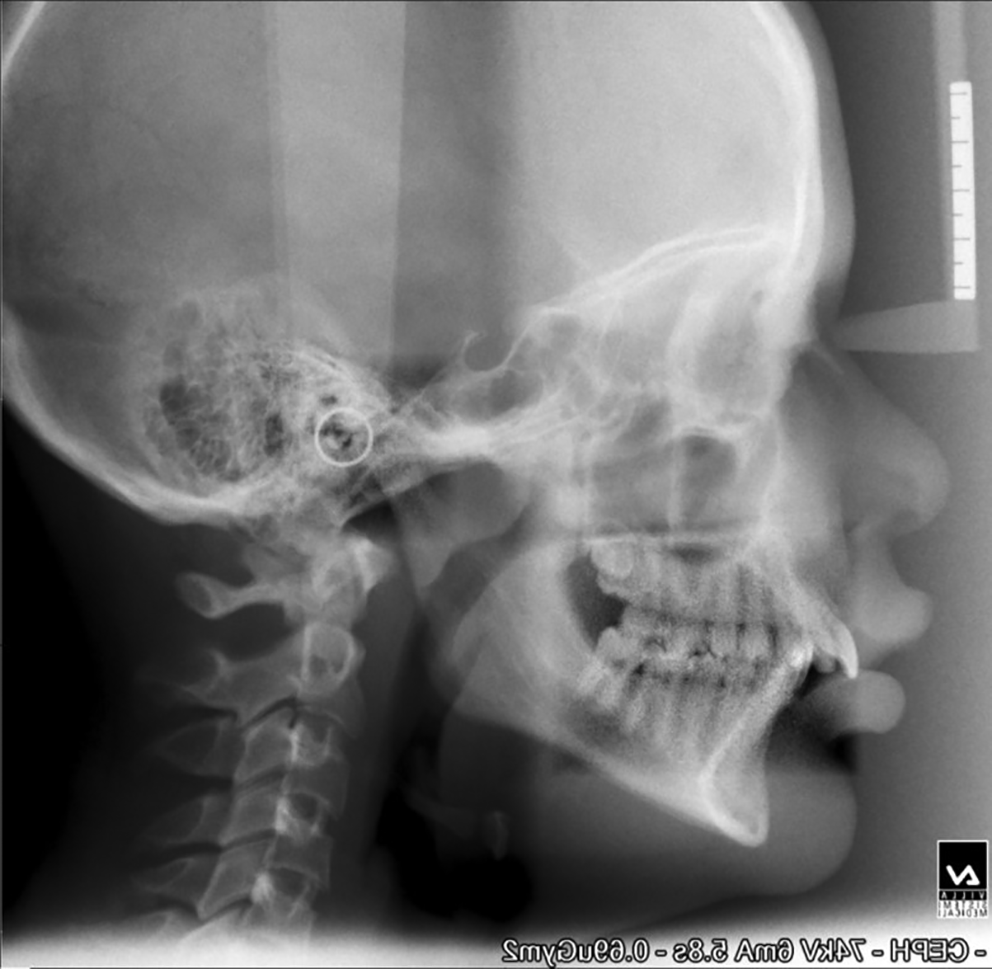

The mean age of the patients at the start of treatment was 12 years. Pre-and post-treatment lateral cephalograms were taken and evaluated for skeletal, dental, and soft tissue changes after wearing a twin block appliance therapy for nine months. Cephalometric changes during treatment are shown in Table 1. Figure 1 shows pre-treatment cephalograms, Figure 2 shows post-treatment cephalograms and Figure 3 shows the superimposition of pre-and post-treatment average digitizations. Twin block appliance wearing resulted in rapid skeletal correction as was evident from a statically significant decrease in angle Point A-Nasion-Point B (ANB), from 7.07±1.98 to 3.33±1.23 degrees (P=0.02); the angle of convexity decreased significantly from 9.87±1.5 to 5.13±1.24 degrees (P=0.01). There was a significant change in Wits appraisal, which decreased from 4.87±0.91 to 3.33±0.72 mm (P=0.04). Angle between Sella-Nasion-Point B (SNB) increased significantly from 74.0±1.46 to 77.9±0.77 degrees (P=0.02). There was a non-significant increase in mandibular length from 86.73±3.34 to 87.8±3.32 mm (P=0.1). The total anterior facial height (increased from 101.73±2.86 to 102.13±2.5 mm, P=0.09) and posterior facial height (increased from 57.27±1.53 to 57.40±1.68 mm, P=0.43) did not show significant changes with no significant increase in Frankfort mandibular angle (FMA increased from 30.73±1.48 to 30.80±1.37 degrees, P=0.67); there were no significant changes in Jarback ratio too (63.73±1.71 to 63.20±1.6, P=0.15); the angle between Sella-Nasion and Gonion-Gnathion (SN-Go-Gn) increased non-significantly from 132.27±2.43 to 132.60±2.29 degrees (P=0.67); the Y-axis increased non-significantly from 56.66±1.75 to 56.86±1.95 degrees (P=0.32). The upper incisor inclination decreased non-significantly from 115.27±1.33 to 113.42±1.65(P=0.12) and the lower incisor increased non-significantly from 100.13±2.23 to 101.80±1.37 degrees, (P=0.08). The nasolabial angle increased by 3.8 degrees and the change was statistically significant (P=0.04). The mean pretreatment (stage 0) value of overjet was 9.60±1.35 mm which was statistically significantly (P=0.01) reduced to 3.6±0.91 mm at 9 months (stage IV) of the twin block therapy. The mean overbite before the start of treatment (stage 0) was 6±0.92 mm. This changed to 2.47±0.83 mm at 9 months of twin block therapy. The change was statistically significant (P=0.03).

d997e343-f282-4d3f-8805-21d883bc0df9_figure2.gif

Figure 2. Post-treatment cephalogram.